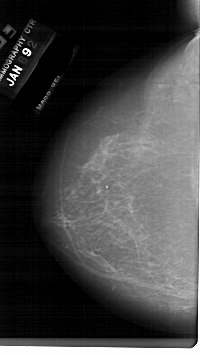

A_1129_1.LEFT_MLO

LEFT_MLO LINES 6736 PIXELS_PER_LINE 3676 BITS_PER_PIXEL 12 RESOLUTION 43.5 NON_OVERLAY